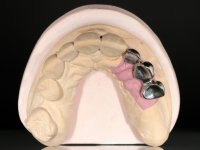

Paciente do sexo feminino, com 69 anos, não fumadora. Apresenta uma prótese combinada no maxilar superior. A porção fixa corresponde a uma ponte metalo-cerâmica de 4 elementos com os dentes 1.3/1.1 e 2.1 como pilares e o dente 1.2 como pôntico. A porção amovível corresponde a uma prótese esquelética de 5 elementos. A retenção da prótese esquelética é feita por um gancho no dente 1.4 e um “attachment tipo t” colocado no dente 2.1.

O estudo imagiológico para a colocação dos implantes, começou com a realização em laboratório de uma guia com dentes em sulfato de bário. Esta guia foi colocada em boca conjuntamente com marcas de referência coladas aos dentes, também em sulfato de bário. A guia foi estabilizada com cera mole. A TAC foi realizada com estas referências colocadas em boca. Após a realização da TAC foi feita uma impressão de arrasto em silicone. Esta impressão foi vazada a gesso em laboratório e posteriormente digitalizada. A digitalização do modelo com as referências foi sobreposta á imagem da TAC, permitindo uma planificação apurada na colocação dos implantes. Na planificação foi decidido colocar 2 implantes no local dos dentes 2.3 e 2.4 evitando-se a zona do 2.2 com pouco osso e o seio maxilar. Este estudo deu origem a uma guia cirúrgica que orientou a colocação dos implantes. Durante o período de osteo-integração a paciente utilizou a prótese removível rebasada com acondicionador de tecidos. A guia cirúrgica mostrou-se também útil na exposição dos implantes mostrando a sua localização precisa e orientando a incisão. A impressão definitiva foi realizada utilizando a técnica de moldeira aberta após eliminação do attachment. No laboratório foi confeccionada uma ponte metalo-cerâmica de 3 elementos com o elemento 2.2 em suspensão. A ponte após verificação e aprovação foi cimentada. A reabilitação apesar de pouco extensa (sem o elemento 2.6) mostrou-se capaz estetica e funcionalmente.